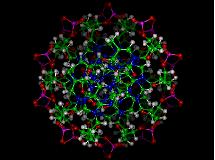

El sensor está construido siguiendo un método consistente en usar piezas de “maquinaria” biológica para crear dispositivos capaces de percibir y diagnosticar pequeñísimas cantidades de ADN y ARN, el material genético donde el código de la vida está inscrito.

La tecnología saca partido al hecho de que, tanto las proteínas como el ADN, se mueven o cambian de forma ante un estímulo externo. Cuando la molécula se une al sensor (que también es una molécula), éste cambia de forma y tira con fuerza de una pequeña partícula, que queda un poco desplazada. Este desplazamiento es detectado ópticamente.

El sensor está construido siguiendo un método consistente en usar piezas de “maquinaria” biológica para crear dispositivos capaces de percibir y diagnosticar pequeñísimas cantidades de ADN y ARN, el material genético donde el código de la vida está inscrito.

La tecnología saca partido al hecho de que, tanto las proteínas como el ADN, se mueven o cambian de forma ante un estímulo externo. Cuando la molécula se une al sensor (que también es una molécula), éste cambia de forma y tira con fuerza de una pequeña partícula, que queda un poco desplazada. Este desplazamiento es detectado ópticamente.